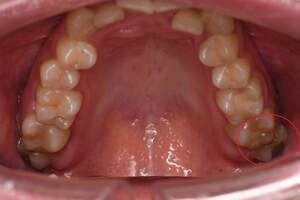

左下の歯茎が腫れている親知らずの症例

- 抜歯前写真(レントゲン、CT等)

左下の親知らず周囲歯肉が腫れていました。

また、手前の歯との間で虫歯もできていました。

口腔内

- Before

- After

半埋伏の親知らずでした。3糸縫合しました。